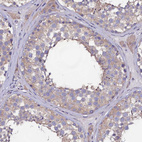

Immunohistochemical staining of human testis shows moderate cytoplasmic positivity in cells in seminiferous ducts.